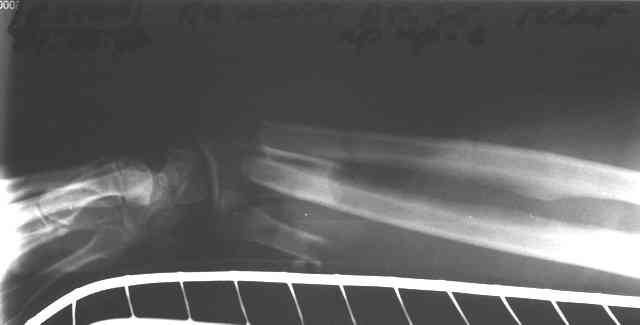

Травма 24 Октября этого года. Диагноз: Неполный травматический отрыв нижней трети предплечья. Выполнено: ПХО открытого перелома, фасциотомия, ЧКДО, шов лучевой артерии. Размозженые мышцы-сгибатели кисти и пальцев экономно иссечены - не сшивались. Спустя месяц выполнена резекция 2,5 см некротизированного конца проксимального отломка лучевой кости. На сегодняшний день по ладонной поверхности предплечья с переходом на наружний край имеется рана с дефектом мягких тканей, выполненная грануляциями с дна и с краев.

По рентгенограммам не видно дефекта лучевой кости после резекции 2,5

см (или снимки до того?).

Прошу прощения - не указал, что после резекции лучевой кости рентгенобследование больной еще не проводилось. На фотогрфиях раны вертикальными черными полосами показаны границы дефекта лучевой кости.